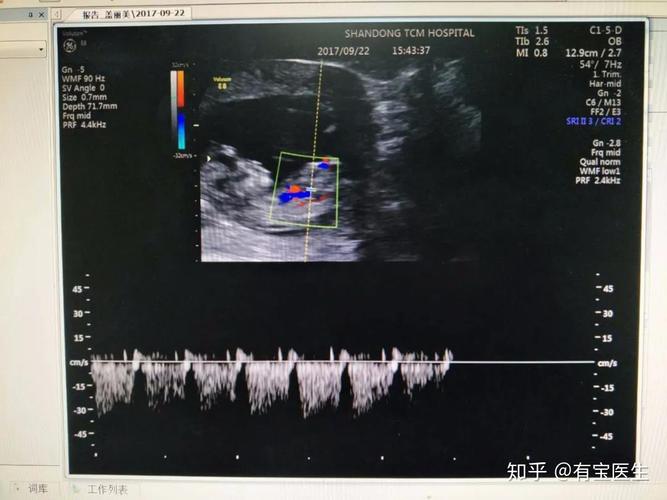

12周静脉导管a波反向

12周静脉导管a波反向,胎儿静脉导管a波反向

dv,a波反向

静脉导管a波反向或消失; 4.脐静脉搏

胎儿静脉导管a波反向

静脉导管a波反向图片

静脉导管超声图

胎儿静脉导管

胎儿静脉导管血流频谱

正常静脉导管频谱图

胎儿静脉导管超声图片